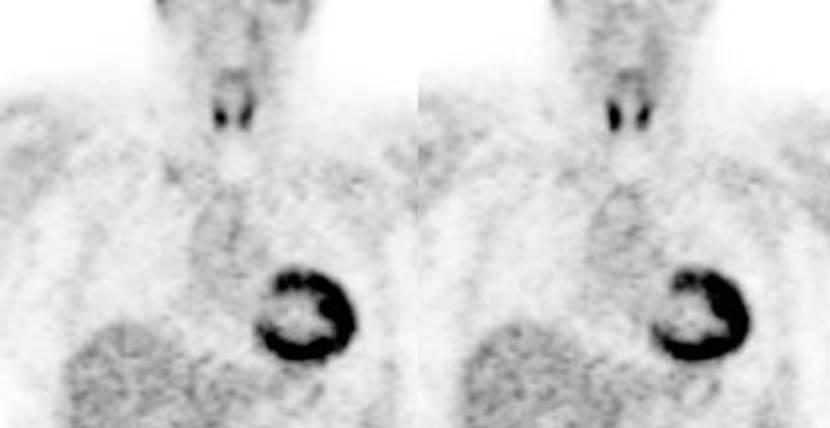

Figure 4 - Myocardial activity: Myocardial uptake can be

very variable. The patient on the left below had a glucose level of 97 prior to

FDG injection. Despite the normal serum glucose, note the intense cardiac

activity in this patient. The patient on the right